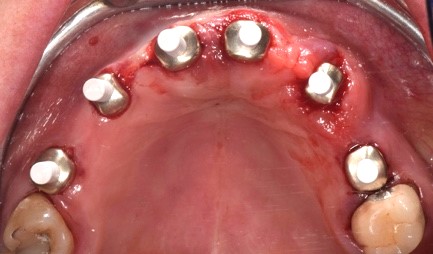

Durante l'intervento chirurgico si posizionava la guida (Fig. 3a) e i siti implantari venivano fresati secondo le sequenze previste. Posizionavamo gli impianti (LYRA ETK, Sallanches, Francia) e gli abutment iPhysio® Profile Designer (Fig. 3 b) che erano selezionati in base al profilo di emergenza desiderato del futuro restauro.

Questi healing abutments vengono avvitati sugli impianti durante la prima o la seconda fase chirurgica. Essi poi restano in posizione durante tutta la guarigione ossea e gengivale e durante la presa dell'impronta, indipendentemente dall'area di impianto. Il Profile Designer iPhysio® viene essere rimosso solo una volta, per posizionare il restauro finale. Gli abutment provvisori in polieter-eter-chetone (PEEK) venivano agganciati agli iPhysio® Profile Designers, sui quali venivano adattati i restauri provvisori (Fig. 3c). Il carico immediato degli impianti è stato eseguito utilizzando una protesi provvisoria in PMMA (Fig. 3d). Al rientro per un controllo, si osservava una corretta guarigione dei tessuti attorno agli impianti e attorno agli abutment iPhysio®.

Fotografia degli impianti appena inseriti con iPhysio® avvitati

Fig. 3(b) Fotografia degli impianti appena inseriti con iPhysio® avvitati.